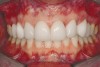

Figure 2a  Corticotomy SFOT. The patient presented with unesthetic anterior bridgework that was placed at age 14 to compensate for congenitally missing Nos. 7 and 10.

Figure 2a

Figure 2c  One week postsurgery with mesial buildups on Nos. 5 and 12 and thin pontics on archwire to conceal spaces during closure.

Figure 2c

Figure 2d  Prerestorative orthodontics was completed in 5 months. Final result 3 years, 4 months after completion.

Figure 2d

Figure 2e  Teeth Nos. 5 and 12 were converted to Nos. 6 and 11, and Nos. 6 and 11 were converted to Nos. 7 and 10. Nos. 4 and 13 were enlarged. Note stability and absence of orthodontic relapse. Before-and-after smiles.

Figure 2e

Figure 2f  Teeth Nos. 5 and 12 were converted to Nos. 6 and 11, and Nos. 6 and 11 were converted to Nos. 7 and 10. Nos. 4 and 13 were enlarged. Note stability and absence of orthodontic relapse. Before-and-after smiles.

Figure 2f